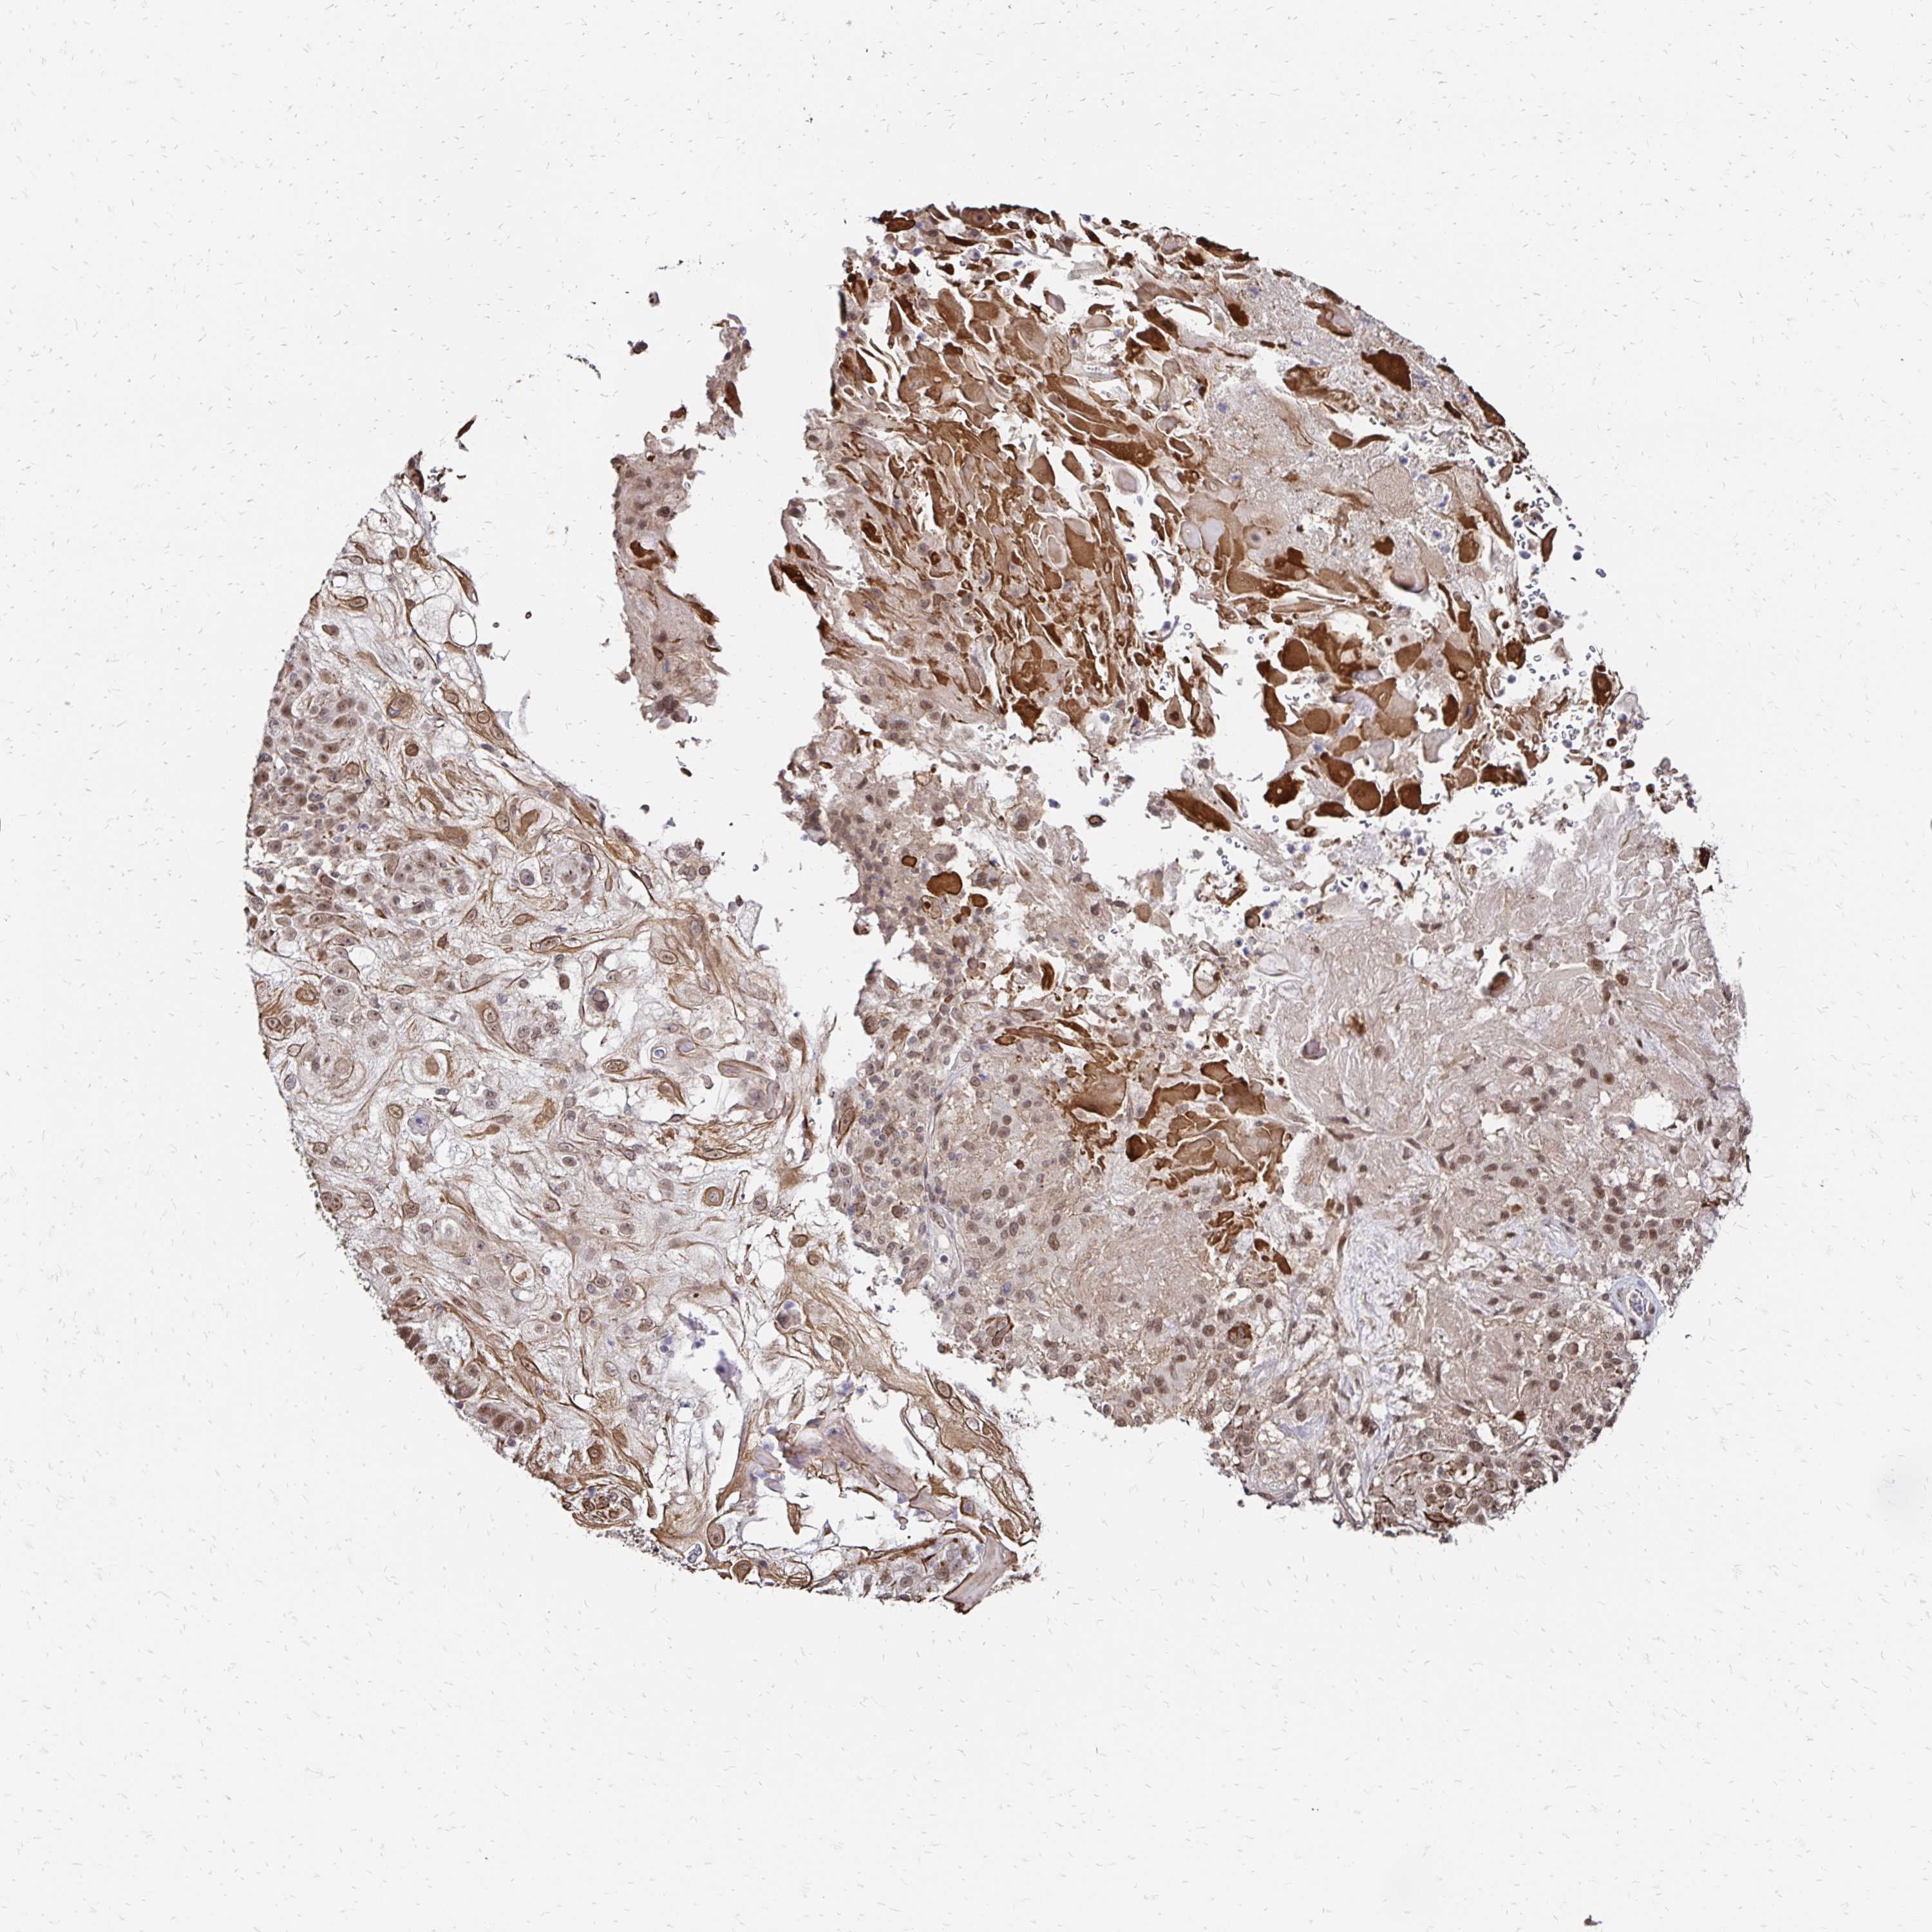

SKIN CANCER - Protein expressioni

A mouse-over function shows sample information and annotation data. Click on an image to view it in a full screen mode. Samples can be filtered based on level of antibody staining by selecting one or several of the following categories: high, medium, low and not detected. The assay and annotation is described here.

Antibody stainingi

Antibody staining in the annotated cell types in the current human tissue is reported as not detected, low, medium, or high, based on conventional immunohistochemistry profiling in selected tissues. This score is based on the combination of the staining intensity and fraction of stained cells.

Each image is clickable and will lead to virtual microscopy that enables deeper exploration of all samples and also displays staining intensity scores, fraction scores and subcellular localization as well as patient and tissue information for each sample.

Antibody HPA045174

Antibody CAB032821

Staining

High

Medium

Low

Not detected

Intensity

Strong

Moderate

Weak

Negative

Quantity

>75%

75%-25%

<25%

None

Location

Nuclear

Cytoplasmic/membranous

Cytoplasmic/membranous,nuclear

Basal cell carcinoma

BCC, high aggressive

Squamous cell carcinoma, NOS

Squamous cell carcinoma, metastatic, NOS